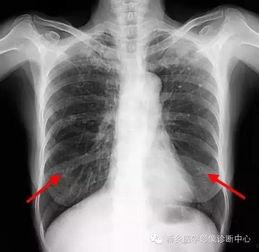

首先,得先弄清楚什么是胸片。胸片,顾名思义,就是通过X射线对人体胸部进行拍摄的一种医学影像检查。它能够清晰地显示出心脏、肺部、纵隔等器官的结构和形态,对于诊断各种胸部疾病有着至关重要的作用。

肺炎是常见的呼吸道疾病,而胸片是诊断肺炎的重要手段。通过观察胸片,医生可以判断肺炎的类型、范围和严重程度,从而制定合理的治疗方案。

肺癌是威胁人类健康的一大杀手,而早期发现是提高治愈率的关键。胸片在肺癌筛查中发挥着重要作用。通过定期进行胸片检查,可以及时发现肺部异常,为早期诊断和治疗提供依据。

在解读胸片时,要关注细节。如肺纹理改变、肺结节、心脏形态等,这些细节往往能够为诊断提供重要线索。